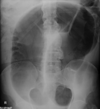

AAA

Ruptured AAA

Autosomal dominant polycystic kidney disease ## Footnote CT of the abdomen (coronal reformats) demonstrates both kidneys to be markedly enlarged by innumerable cysts ranging in size from a few millimetres to multiple centimetres. These cysts also vary in density: most are near-water density, some are hyperdense, others are calcified. Also present are numerous cysts in the liver. The pancreas is unremarkable. Features are consistent with autosomal dominant polycystic kidney disease, which was subsequently confirmed.

Sigmoid volvulus ## Footnote dilation causes the classic coffee-bean sign, a pathognomonic of sigmoid volvulus.